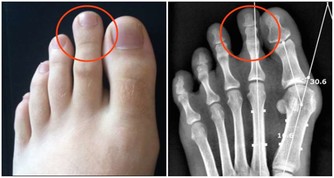

膝關節尤其是人體所有關節、軟骨構造中最為複雜的部位,

包括髕骨、大腿股骨、小腿脛骨、兩個半月狀軟骨及四條韌帶,活動機轉相當複雜。

加上膝關節必須承受人體全部或數倍的重量,

加上日常跑、跳、上下樓梯、背負重物、穿高跟鞋等因素,

膝蓋的受力更大,是全身關節中最容易退化的部位。

膝關節

膝關節可以說是退化性關節炎的最大宗。關節就如同車子的輪胎般,如果常煞車、摩擦多,輪胎就會提早報銷。門診中患者常見的主述症狀如下:

⑴疼痛加上軟痠及卡住的感覺,多屬半月軟骨的問題。

⑵下樓梯時膝蓋痠軟,多屬髕骨軟化,以女性居多。

⑶從坐姿站起時兩腿感到痠軟,通常屬於骨小樑退化。

⑷關節感到卡卡的,且無法伸直或彎曲,則是半月板破裂。